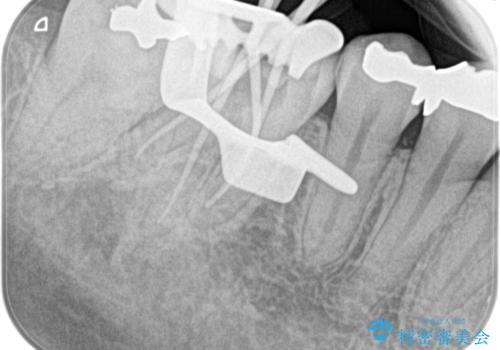

【根管治療】昨日から眠れないぐらい歯が痛い

- 昨日から夜も眠れないぐらい痛いことを主訴に来院されました。

検査の結果、不可逆性歯髄炎の診断とし根管治療を行なっております。

- 精密根管治療(イニシャルケース,大臼歯):122,000円、ファイバーコア:22,000円費用は治療当時の料金となります